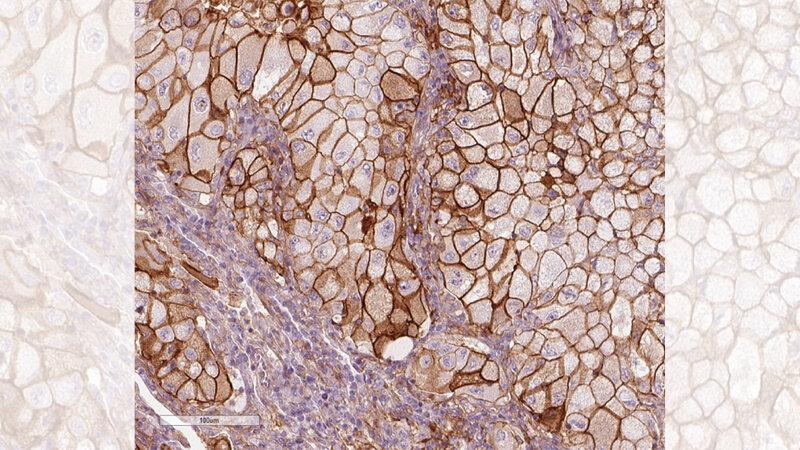

Den Einfluss von PD-L1 auf die Prognose bei Lungenkrebs hat Dr. Karolina Edlund vom Leibniz-Institut für Arbeitsforschung an der TU Dortmund (IfADo) erforscht. Bei Krebs kommen verschiedene Therapien zum Einsatz. Von besonderem Interesse ist die Krebsimmuntherapie, bei welcher von Krebszellen zunächst gehemmte Immunzellen wieder aktiviert werden. Für die Aufklärung der zugrunde liegenden Mechanismen haben James Allison und Tasuku Honjo 2018 den Nobelpreis für Medizin erhalten. Bei dieser innovativen Therapieform ist es wesentlich zu wissen, wie sich die Krebszellen gegen das Immunsystem zur Wehr setzen. Dazu nutzen Krebszellen beispielsweise das Molekül Programmed Death Ligand 1, kurz PD-L1. Mittels PD-L1 kann die Krebszelle Rezeptoren auf den Immunzellen blockieren und so die Zelle in einen Dornröschenschlaf versetzen. Dr. Karolina Edlund vom IfADo hat in einer aktuellen Studie grundlegende Beobachtungen gemacht, um den Einfluss des Immunsystems besser zu verstehen.

Edlund und internationale Kollegen untersuchten dazu zelluläre und molekulare Profile von nicht kleinzelligen Lungentumoren (NSCLC, non-small cell lung cancer), der häufigsten Lungenkrebsart. Die Daten stammten aus zwei großen Kohorten mit 705 Lungenkrebspatientinnen und -patienten aus Schweden. Diese Patienten hatten relativ kleine Tumore, so dass sie operiert werden konnten.

Die Forschenden konnten anhand der umfangreichen Daten darlegen, dass eine hohe Zahl bestimmter Immunzellen im Tumorgewebe eindeutig mit einer besseren Prognose einhergeht und damit frühere Studien bestätigen. Bei den Immunzellen handelt es sich um Plasma- und T-Zellen. Plasmazellen können Antikörper produzieren. T-Zellen prüfen Zelloberflächen auf abweichende Muster, zerstören als fremd erkannte Zellen oder schlagen Alarm und aktivieren weitere Immunzellen. Die Studienergebnisse belegen: Je mehr T- und Plasmazellen im Tumorgewebe vorhanden sind, desto länger ist die Überlebenszeit. Diese günstige Wirkung war in schnell wachsenden Tumoren sogar stärker ausgeprägt.